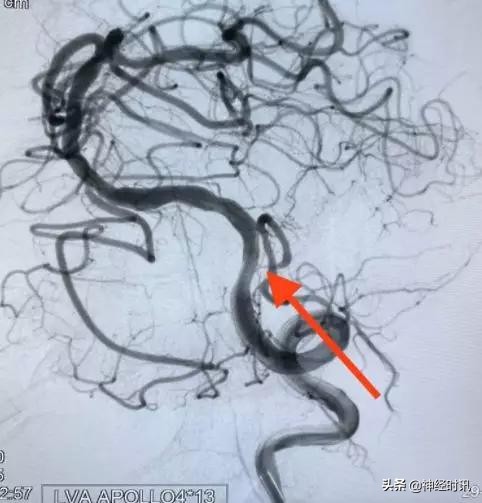

病例2(下图)是一个反复头晕发作的病例,通过脑血管造影我们发现患者的右侧椎动脉已经闭塞(黄箭),左侧椎动脉颅内段95%的狭窄(红箭),这种狭窄本身不难处理,但是,同侧粗大的小脑后下动脉发自于狭窄段,而且其起始段已经狭窄呈线样(小白箭),可谓藕断丝连!

在与家属充分沟通后还是决定治疗。我们进一步精细化了手术方案,决定术中保护小脑后下动脉。我们先放置一条柔软的微导管在小脑后下动脉(绿箭),然后再对狭窄实施扩张(蓝箭)。这样就极大地提高了保护分支的概率。

扩张完后再置入支架。经过这样的技术细化,我们可以看到在狭窄被治疗的同时,很好地保护了分支(红箭)。